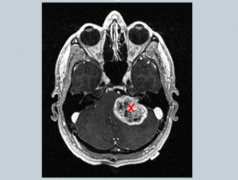

髓母细胞瘤一词较早由贝利和库欣于1925年提出,指儿童时期常见...